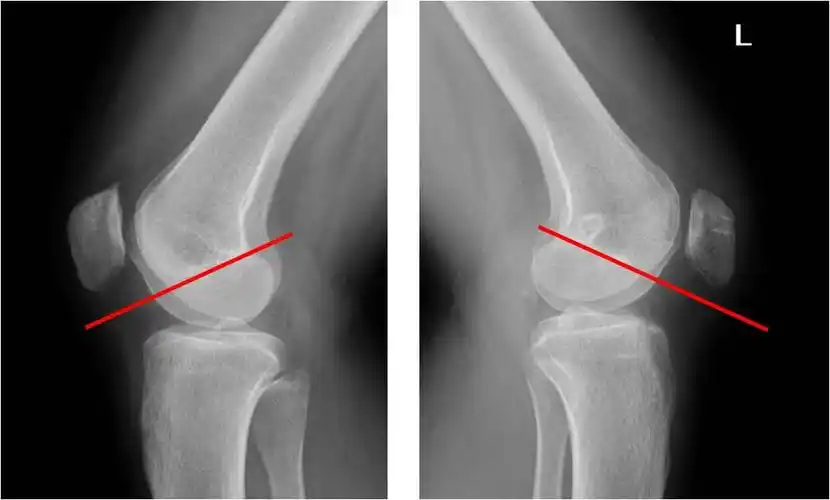

复发性髌骨脱位和习惯性髌骨脱位的手术治疗